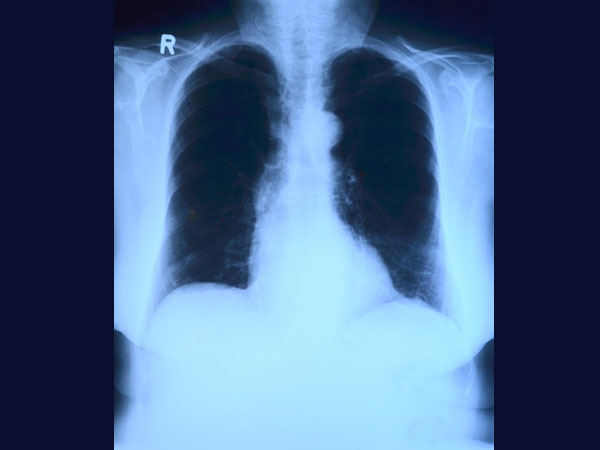

புகைப் பிடிப்பதால் செல் அழிவு நுரையீரலில் அதிமாகிவிடும். அதிலுள்ள கார்பன் மோனாக்ஸைடே காரணம். நீங்கள் உற்று கவனித்தீர்களேயானால் சிலர் வருடக் கணக்கில் புகை பிடிப்பார்கள் ஆனால் அவர்களுக்கு ஏதும் ஆகாது. இன்னும் சிலருக்கு ஒரு வருடத்திலேயே புற்று நோய் தாக்கம் வந்துவிடும்.

இதற்கு காரணம் ஒவ்வொரு மனிதனுக்கும் உள்ளுறுப்புகள் தனித் தன்மையுடன் இருக்கும். அதன் பொறுத்தே அவர்களுக்கு நோயும் உண்டாகும். எனவே அவருக்கு ஒன்னும் ஆகலை நமக்கும் எதுவும் ஆகாது என்ற எண்ணத்தை விட்டுவிடுங்கள்.அதோடு புகை, பான் ஆகிய பழக்கங்களையும் ஒழித்திடுங்கள். நுரையீரல் புற்று நோய் வராமல் பாதுகாக்கலாம்.

தொடர்ந்து எக்ஸ் ரே, புற ஊதாக் கதிர் மற்றும் சக்தி வாய்ந்த கதிர்களின் தாக்கத்தில் இருந்தால் அவை சருமத்தில் ஊடுருவி ஜீன்களின் மாற்றத்தை உண்டாக்கி, புற்று நோய்களை தருவிக்கும். குறிப்பாக சருமப் புற்று நோய் வருவதற்கான சாத்தியங்கள் அதிகம்.